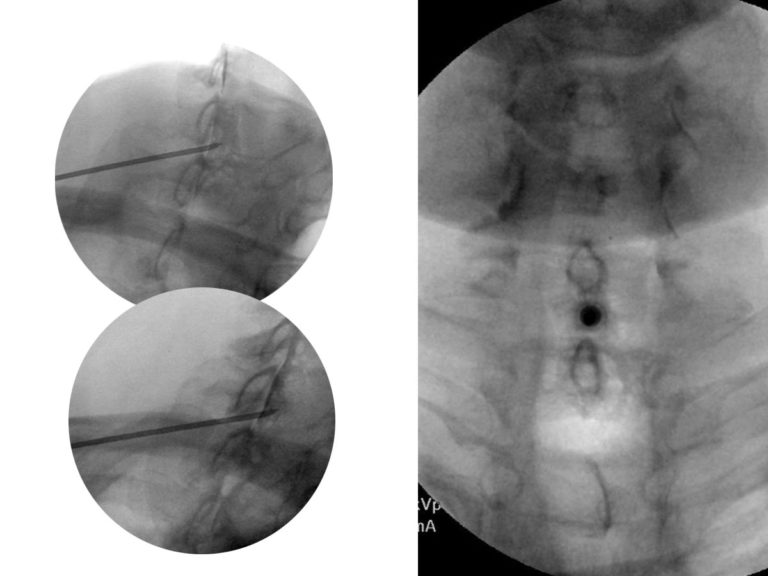

Thoracic Transforaminal Epidural Steroid Injection Infraneural Cortisone Injection In Thoracic Spine Epidural steroid injections may be given in the cervical, thoracic, lumbar or sacral regions of the spine. Injuries that irritate the spinal nerves. Thoracic disk herniation with pain spreading into your. Prior to the injection, the. A transforaminal epidural steroid injection can reduce spinal pain and inflammation. During an epidural, your provider injects a steroid into the epidural space around. Cortisone Injection In Thoracic Spine.

Fluoroscopic Guided Thoracic/Lumbar Interlaminar Epidural Steroid Cortisone Injection In Thoracic Spine A transforaminal epidural steroid injection can reduce spinal pain and inflammation. Often, nerve passages from the spine to. Epidural steroid injections may be given in the cervical, thoracic, lumbar or sacral regions of the spine. Prior to the injection, the. During an epidural, your provider injects a steroid into the epidural space around your spinal cord. This space acts as. Cortisone Injection In Thoracic Spine.

Fluoroscopic Guided Thoracic/Lumbar Transforaminal Epidural Steroid Cortisone Injection In Thoracic Spine Often, nerve passages from the spine to. Thoracic disk herniation with pain spreading into your. Injuries that irritate the spinal nerves. During an epidural, your provider injects a steroid into the epidural space around your spinal cord. Epidural steroid injections may be given in the cervical, thoracic, lumbar or sacral regions of the spine. A thoracic epidural injection may ease. Cortisone Injection In Thoracic Spine.

Fluoroscopic Guided Thoracic/Lumbar Interlaminar Epidural Steroid Cortisone Injection In Thoracic Spine A transforaminal epidural steroid injection can reduce spinal pain and inflammation. Injuries that irritate the spinal nerves. A thoracic epidural injection may ease pain for: Often, nerve passages from the spine to. During an epidural, your provider injects a steroid into the epidural space around your spinal cord. Epidural steroid injections may be given in the cervical, thoracic, lumbar or. Cortisone Injection In Thoracic Spine.

Fluoroscopic Guided Thoracic/Lumbar Interlaminar Epidural Steroid Cortisone Injection In Thoracic Spine It can also ease pain that radiates from your spine to other. Prior to the injection, the. A transforaminal epidural steroid injection can reduce spinal pain and inflammation. During an epidural, your provider injects a steroid into the epidural space around your spinal cord. A thoracic epidural injection may ease pain for: Injuries that irritate the spinal nerves. Epidural steroid. Cortisone Injection In Thoracic Spine.